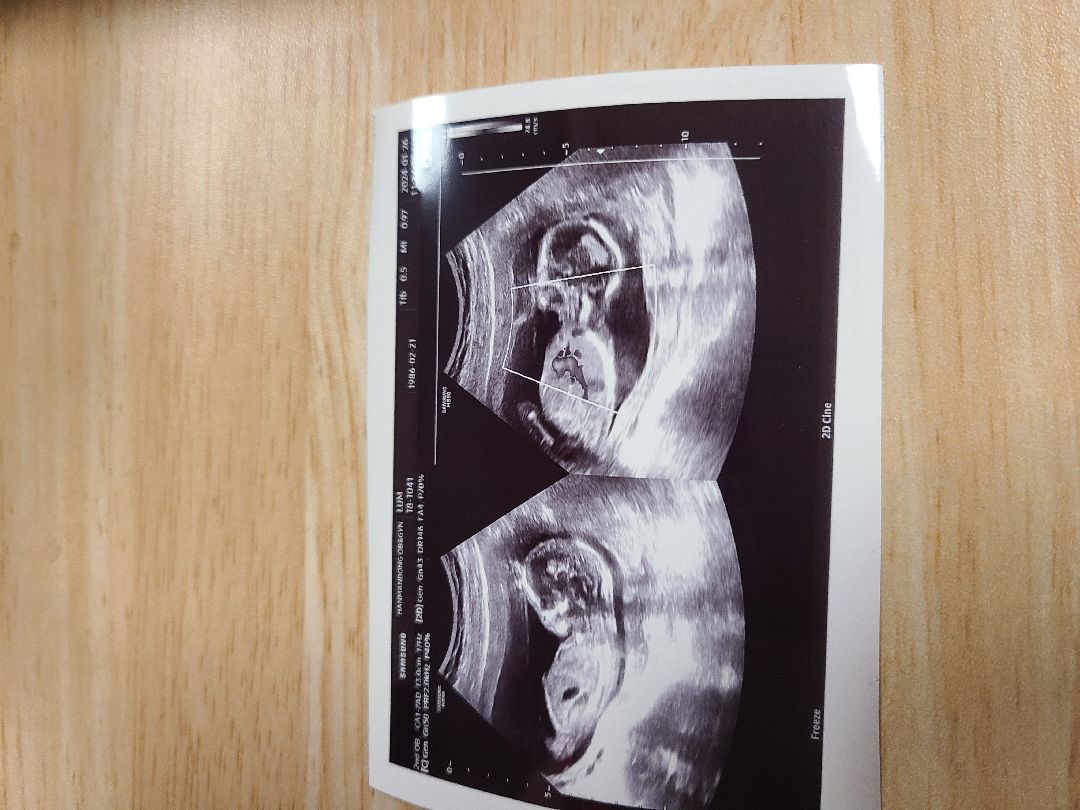

16주 태아 각도법 알려 주세요

16주 초음파보고 왔는데 원장님이 다리 사이도 안보여 주시고 아직 에매하다고 하셔서요..딸이든 아들이든 상관없는데 노산이고 첫째라 많이 궁금해서요~각도법 으로 아시는분 알려 주세요~^^

16주는 각도법안될거에요~~ 남자아이는 나와있고 여자아이는 이미들어갈시기라서..ㅎㅎ